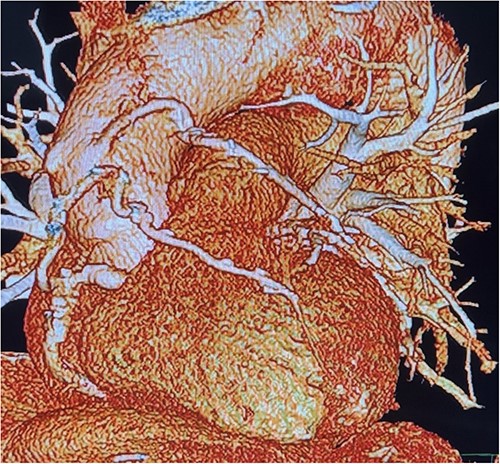

Before resternotomy, a cardiopulmonary bypass was performed via the right common femoral artery and vein. The RIMA was harvested in a semi-skeletonized fashion because skeletonized IMA is in general, longer than pedicled IMA. However, the RIMA could not reach the LAD in the present case due to cardiomegaly. Therefore, the proximal end of the RIMA was cut to use as a free graft. Subsequently, the proximal portion of the patent RA graft was tried to dissect as a proximal anastomosis site, but it was not possible due to severe adhesion of the surrounding tissue. Therefore, we decided to anastomose the proximal RIMA to the proximal right coronary artery (RCA) as the inflow site. The distal RIMA was anastomosed to the LAD as usual (Fig. 1). The postoperative course was uneventful, and the patient was discharged 11 days after the operation. A 3-month postoperative coronary angiogram showed the patency of the RA and RIMA conduits (Fig. 2). Moreover, from coronary computed tomography angiography after 6 years, it was confirmed that it was still patent (Fig. 3).

Cardiac computed tomography showing patency of RIMA to LAD 6 years after redoing CABG operation.